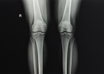

'Osteotomy' boon for young patients with arthritis: Orthopedic surgeons